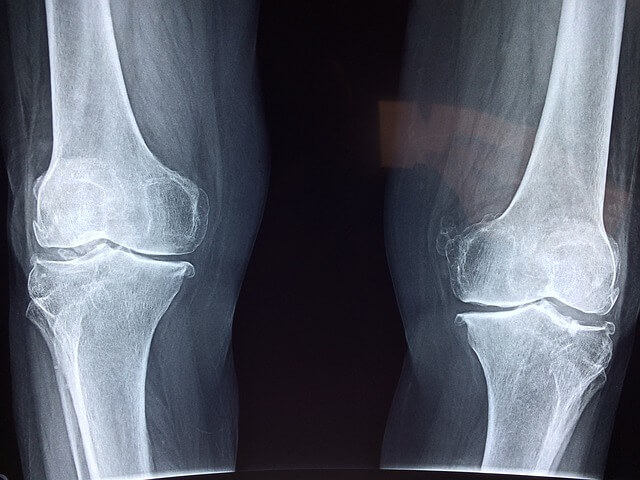

▶ 관절염

무릎관절의 염증으로 인해 발생하는 통증,고령자,비만,부상, 유전적 요인등 다양합니다.

▶퇴행성 변화

나이가 들어감에 따라 무릎관절의 퇴행성 변화가 발생할 수 있습니다. 잘못된 자세 반복된 자세 등이 원인입니다.